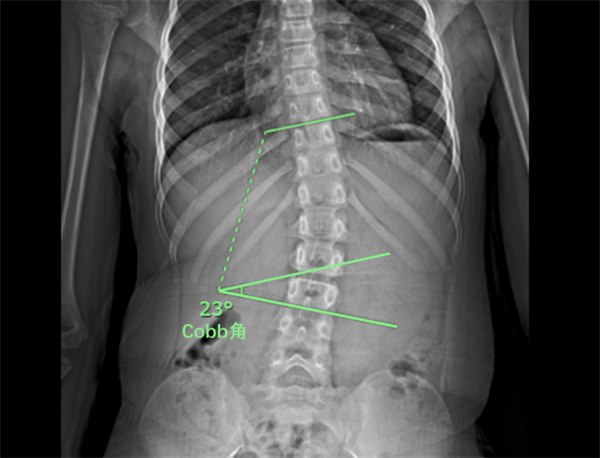

脊柱侧弯又称脊柱侧凸,是脊柱冠状面、矢状面及水平面的三维畸形。光看文字不理解,我们直接来看图:正常的脊柱形态从背面观察是一条竖直的直线(图1),通过躯干正中线的位置,而从侧面来看分为颈、胸、腰和骶四个生理弯曲,呈S形(图2)。当发生脊柱侧弯时,各个椎体之间会出现不同程度的侧屈和旋转。站立位全脊柱X光片上显示Cobb角≥10°的侧方弯曲即可诊断为脊柱侧弯(图3)。根据弯弧可分为:“C”弯、“S”弯或者胸弯、胸腰弯、腰弯。

图3. Cobb角测量法